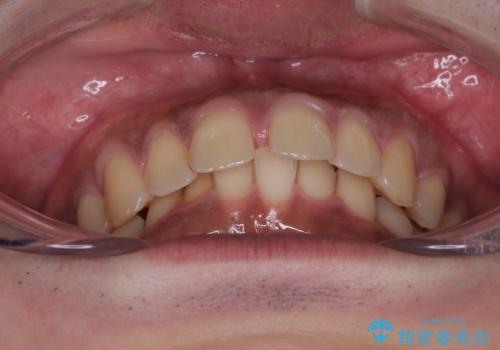

- 上の前歯の正中離開(すきっ歯)と、下顎前歯部の叢生(デコボコ)を主訴に来院された患者様の症例です。

「目立ちにくい装置で治療したい」とのご希望があり、透明のマウスピース矯正であるインビザラインを用いて矯正治療を行いました。

インビザラインは装置が透明で、周囲に気づかれにくいことが大きなメリットです。